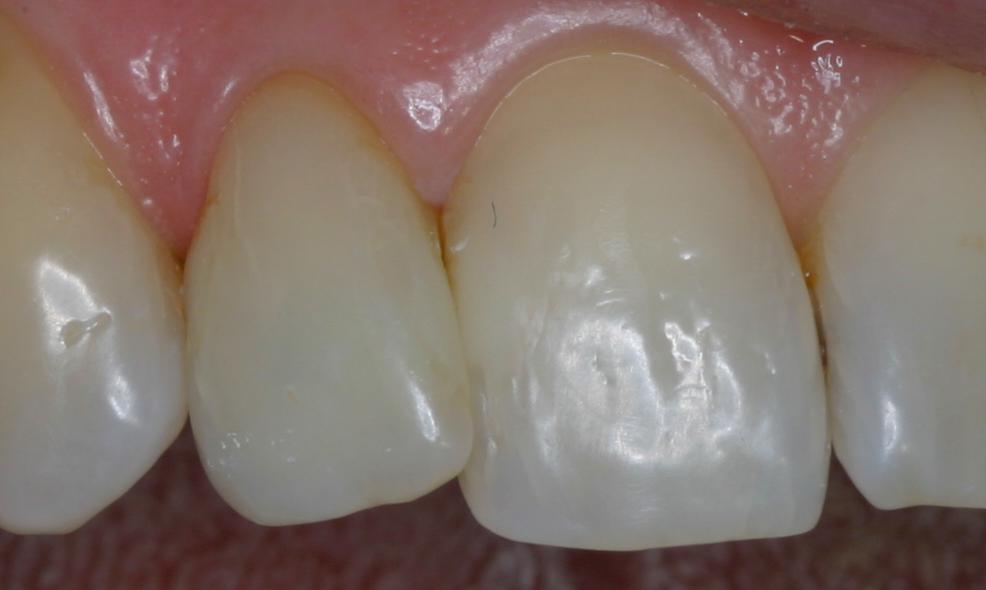

Un ancien traitement de racine est présent sur l'incisive gauche

Il a coloré la base de la dent

Au bout de 2 mois et 4 séances de blanchiment interne